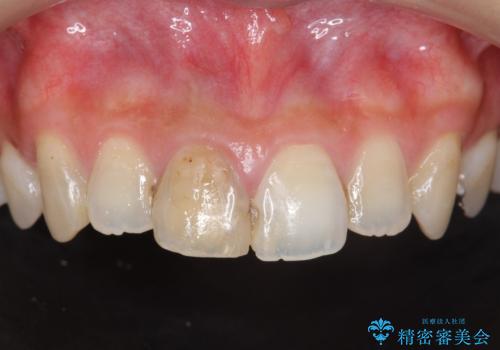

[ 前歯部セラミック治療 ]目立つ前歯をきれいにしたい

![[ 前歯部セラミック治療 ]目立つ前歯をきれいにしたいの症例 治療前](https://seimitsushinbi.jp/wp/wp-content/uploads/2022/04/9401b504f43bc2ce4a7dae12d09aa5c3-500x350.jpg?v=1649930447)

![[ 前歯部セラミック治療 ]目立つ前歯をきれいにしたいの症例 治療後](https://seimitsushinbi.jp/wp/wp-content/uploads/2022/04/21c4bdad5350d81f411ab868ac0877c9-500x350.jpg?v=1649930472)